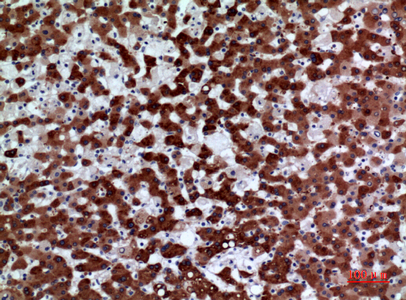

![FMO3 antibody [N2C2], Internal detects FMO3 protein at cytosol on human normal liver by immunohistochemical analysis. Sample: Paraffin-embedded normal liver. FMO3 antibody [N2C2], Internal (GTX103521) dilution: 1:500.